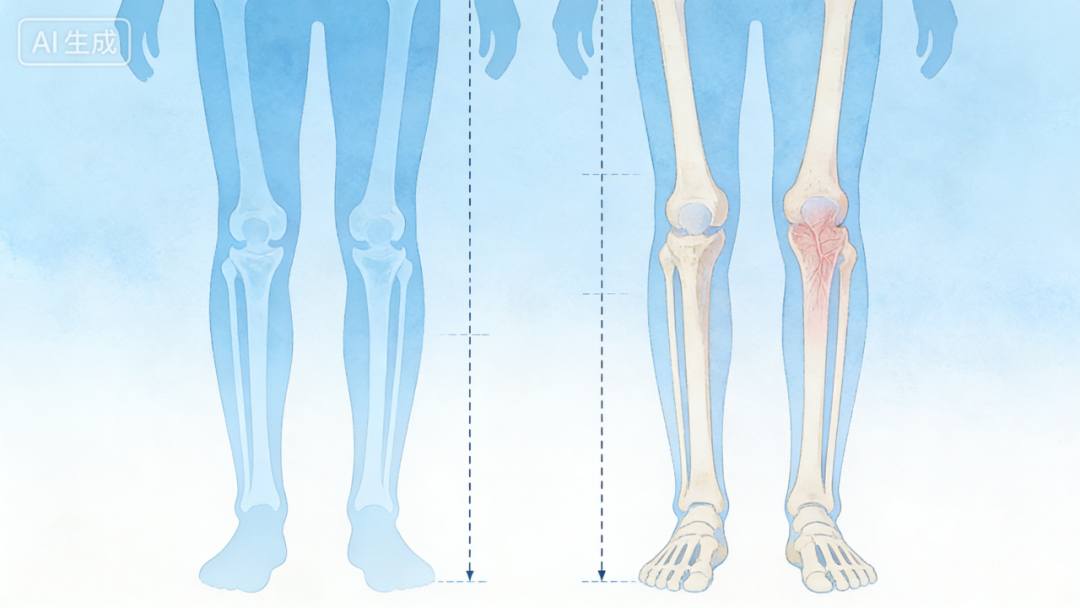

如果发现

肢体慢慢变弯

两侧肢体(腿 / 胳膊)长度不一样

局部隐隐作痛

别不当回事,这些可能是骨纤维异常增殖症的早期表现,及时就医评估能避免畸形加重。